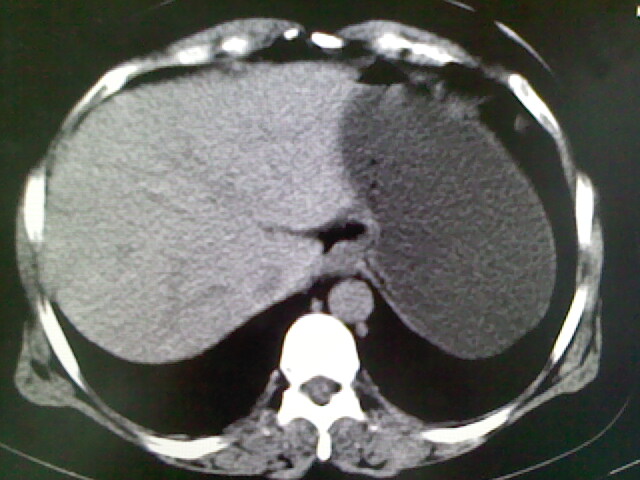

以下是引用卜一在2009-4-2 13:26:00的发言:[br]胆囊颈部结石伴胆囊炎!另:建议增强,待除外肝内占位及胆囊占位!

以下是引用liaoqiang在2009-4-2 16:23:00的发言:[br]胆囊是否切除?胆囊颈区致密影考虑金属夹?结石?肝脏右叶低密度影,考虑增强。